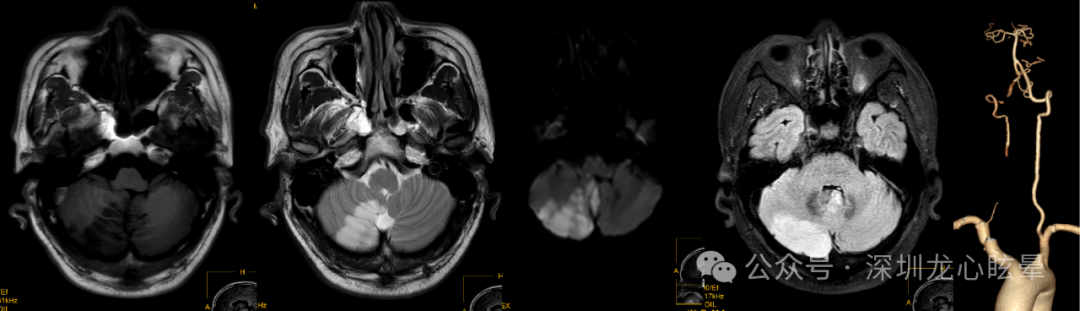

脑干病变引起血管源性头晕/眩晕:支配眼动与姿势平衡的神经整合中枢及传导束主要位于延髓背侧、脑桥被盖与中脑顶盖等区域。这一区域血供丰富,来自延髓外侧动脉、AICA、PICA的诸多分支在此形成吻合支,单纯的小梗死灶在临床较为少见,但该区局限性小梗死灶一旦出现,临床上常以类似前庭神经炎的症状就诊。脑干区域虽较为狭小,但重要核团众多,与人体平衡感知、前庭眼动反射相关的诸多核团均位于该区,如前庭神经核群、第8颅神经在脑桥延髓交界处出入脑干段区、眼动控制核团(如舌下神经前置核、Roller核、闰核、旁中央束细胞组)等,上述部位病变除了引起头晕、眩晕及失衡症状外,通常伴随邻近结构损害相关症状和体征,需重视神经系统查体以及脑干综合征的识别(延髓背外侧综合征、延髓内侧综合征、脑桥被盖下部综合征、核间性眼肌麻痹等)。若病变仅损害延髓-脑桥背侧的前庭神经核、舌下周核复合体或第Ⅷ对脑神经延髓-脑桥交界入颅段可表现为中枢性血管源性头晕/眩晕,其中 REZ区域因供血动脉吻合支丰富,梗死较为罕见。

图3 一例右侧延髓急性脑梗死(椎动脉夹层)

图4 一例延髓海绵状血管瘤